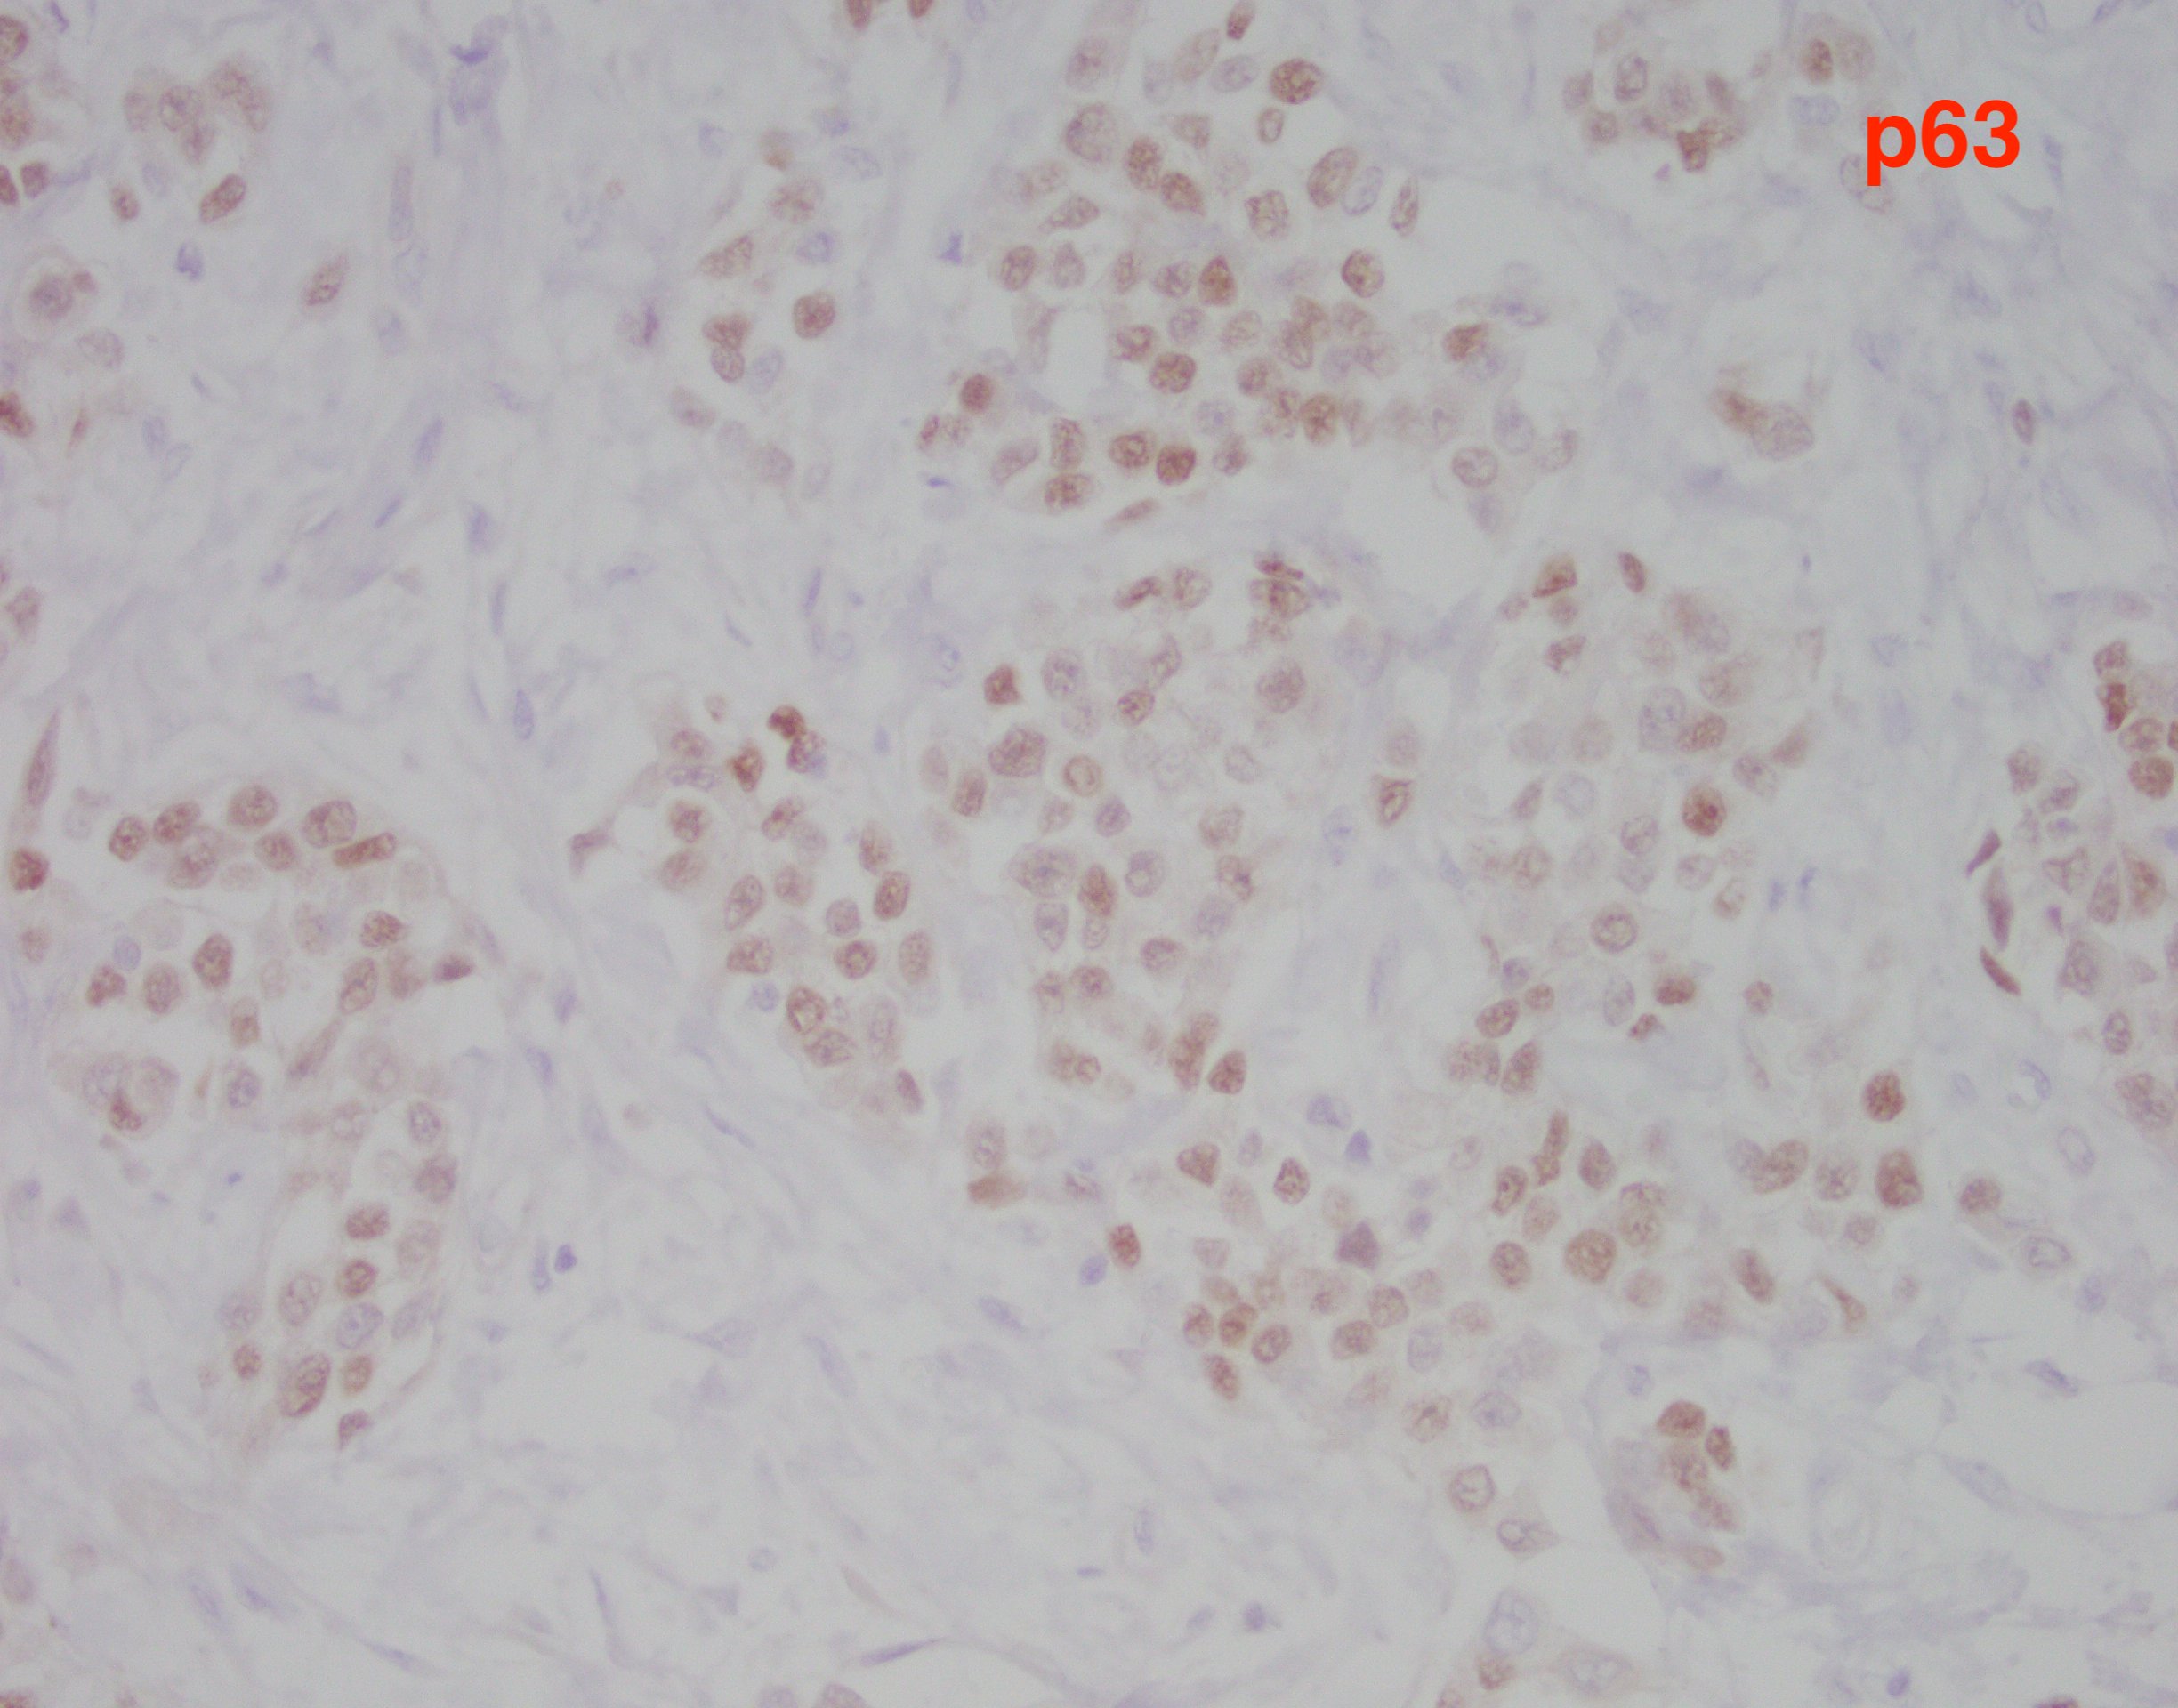

The findings in this case show a diffuse, infiltrative, and discohesive tumor extending into the perivesical adipose tissue. There is extensive perineural and lymphovascular invasion. Focal areas show urothelial carcinoma in situ. Tumor cells have eosinophilic cytoplasm, and nuclei are eccentrically located with focal signet ring cell features. Staining with p63 and GATA3 was performed and shows positivity in both stains.

These features are all consistent with the plasmacytoid variant of urothelial carcinoma. Typically, this variant grows in a linitis plastica-like manner. Tumor infiltration is diffuse, in single cells or cords. Characteristically, tumor cells exhibit eccentric nuclei and/or signet ring cell morphology. Of note, these tumors stain similar to usual urothelial carcinomas, but also strongly express CD138 and lose E-cadherin expression. Most tumors are locally advanced at the time of diagnosis and are highly aggressive.